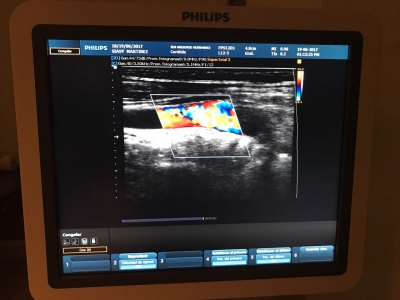

La ecografía doppler de la carótida es una prueba sencilla e indolora que combina dos tipos de Sonografía para detectar obstrucciones en las arterias carótidas. La Sonografia es un tipo de análisis que utiliza ondas sonoras para producir una imagen del interior de su cuerpo. Las arterias carótidas se encuentran a lo largo de ambos lados de su cuello. Arterias carótidas bloqueadas son un importante factor de riesgo para el accidente cerebrovascular.